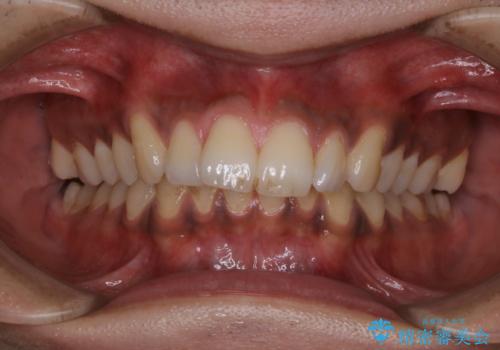

他人から口臭を指摘されて初めてのPMTC

- 他人から口臭を指摘されたので歯のクリーニング希望との事でした。

PMTC60分コースを行いました。

PMTCとはProfessinnal Mechanical Tooth Cleaning・専門器具による歯の機械的な清掃です。

バイオフィルム(細菌の塊)を破壊し、歯の表面をツルツルにすることでお口の中の細菌数を減らし歯周病のリスクが定着するのを防ぎます。更に、歯に新しい汚れがつきにくい状態になります。

PMTCを行うことにより、虫歯・歯周病・口臭予防だけでなくスッキリと爽快感が得られたり、見た目も清潔感のある状態になるため、今後の治療などお口に対するモチベーションUPにも繋がります。